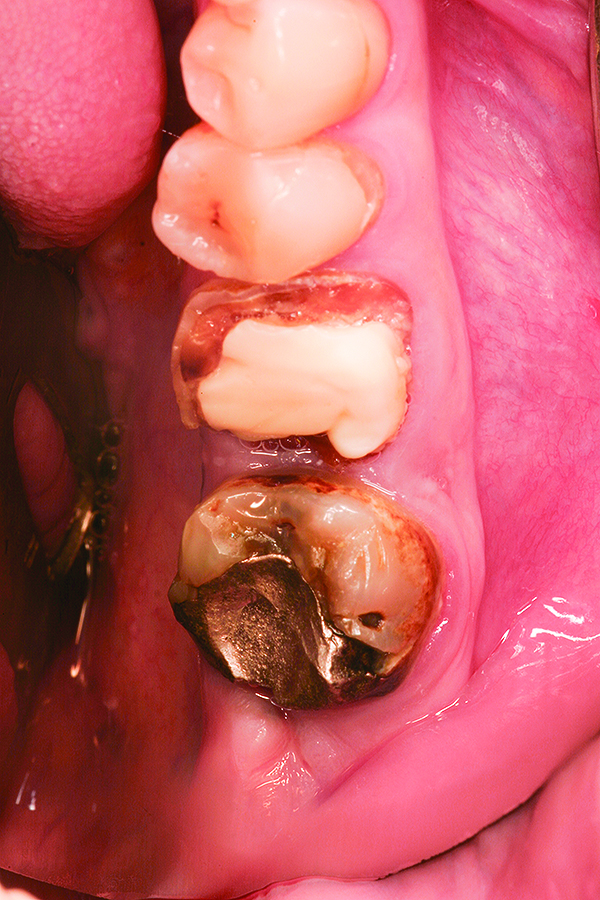

Fig 15. Case 3: Hopeless mandibular molar prior to extraction.

Figure 15

Fig 16. Note the significant dehiscence defect in the buccal wall prior to tooth extraction.

Figure 16